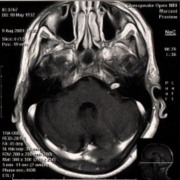

听神经瘤是脑内桥小脑角区(CPA)比较常见的脑肿瘤,中老年人多见。听神经瘤发生于前庭神经雪旺氏细胞鞘,因为面神经、听神经、前庭上和前庭下神经组...